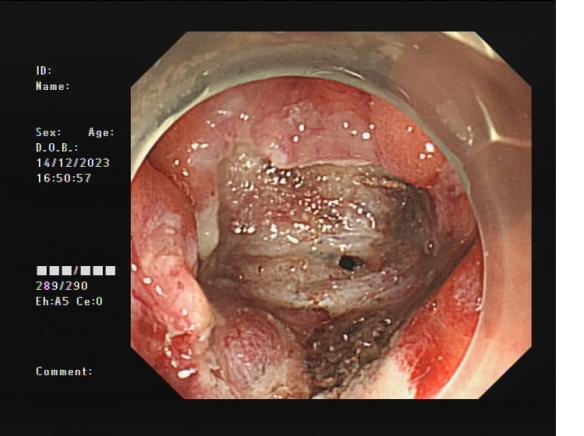

胃底間質瘤 內鏡下全層切除術后創面 切除后標本

內鏡下全層切除術(EFTR):治療消化道黏膜下腫瘤(最主要):起源于固有肌層深層、部分腔外生長、與漿膜層密不可分;少部分抬舉征陰性消化道癌前病變和早期癌;少部分困難解剖部位結腸病變(如結腸憩室內腺瘤)等。